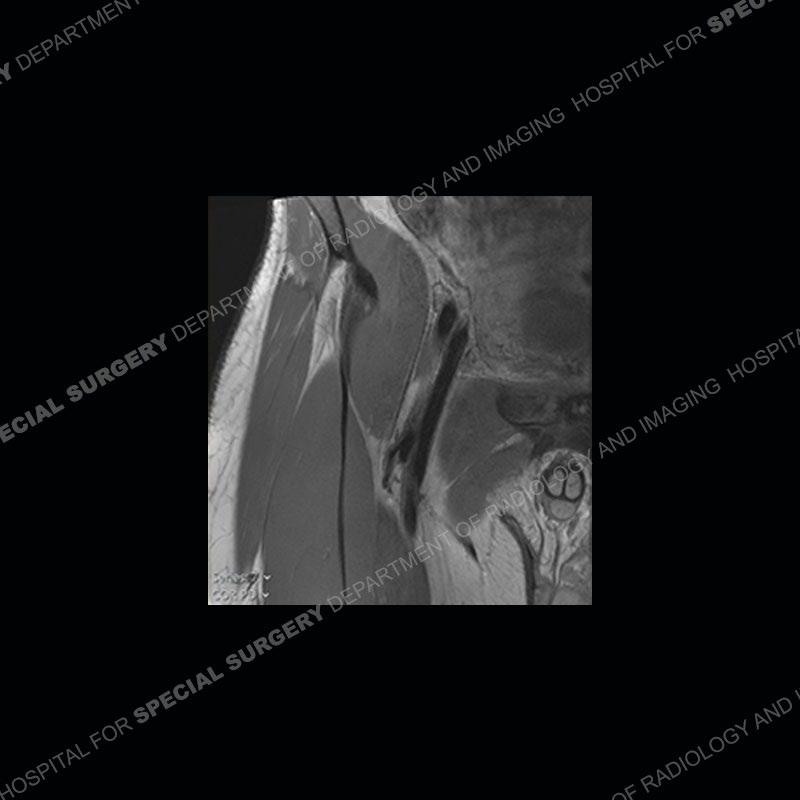

Subsequent MRI in a very short time interval shows markedly increased abnormality of the ramus and increased edema and “mass” of the soft tissue. Post contrast imaging shows multiple, rim enhancing collections of the soft tissue and similar albeit less conspicuous enhancing collection of the ramus.

The repeat MRI, with the marked degree of increased abnormality of the bone and soft tissue shifted the diagnosis to a high degree towards infection. Even the most aggressive of neoplasms would not have that the degree of change in a 3-day time span. The CT study was shown before the repeat MRI but actually occurred just after the repeat MRI. It helped confirm the destructive process of the ramus and particularly the abnormal architecture along the inferior margin. The patient went on to have a CT guided aspiration of one of the soft tissue collections with 4cc of purulent fluid obtained. A surgical irrigation and debridement of the bone and soft tissue was performed. A PICC line was placed and the patient is currently undergoing IV antibiotic treatment with a possible repeat irrigation and debridement.